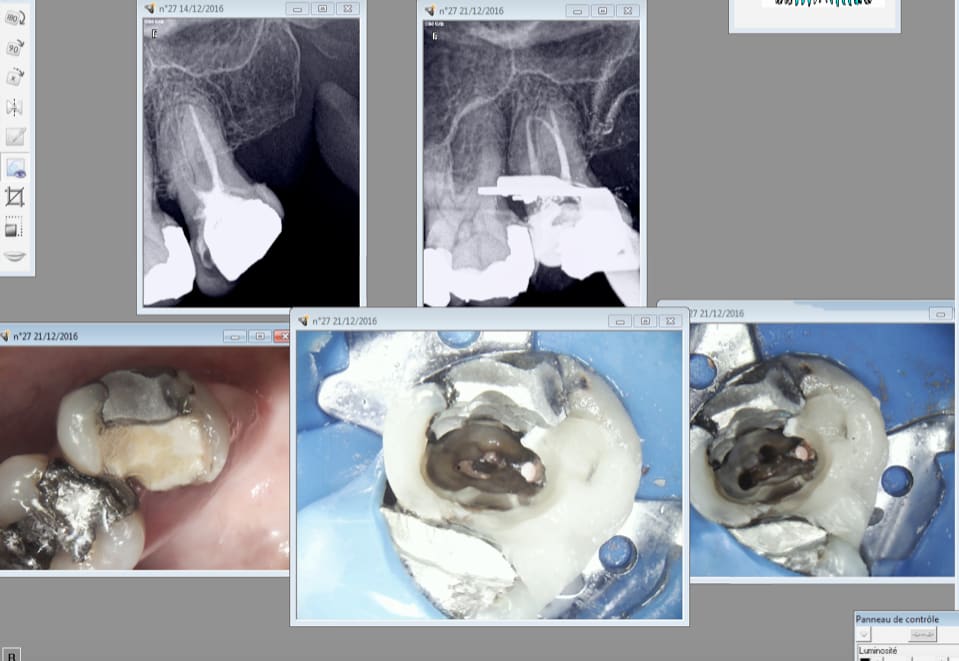

> Franchement un tel soin ne mérite même pas 20 euros. Alors arrêter pour certains

> de jouer les pleureuses. Tant que certains dentistes travaillerons de la sorte

> les gouvernants auront du grain à moudre. Et n'allez pas me dire que l'endo ne

> vaut rien donc on bâcle. Comment le dentiste peut justifier son prix de prothèse

> (IC et couronne) avec une telle "merde" en endo. Franchement même avec le

> plafonnement il prendrait encore trop cher. C'est cela qui nous fait mal.

Pas d'accord l'endo vaut son prix ( sur le cas en photo) et la prothèse aussi. On serait beaucoup plus cher en prothèse si on rattrapait. -)